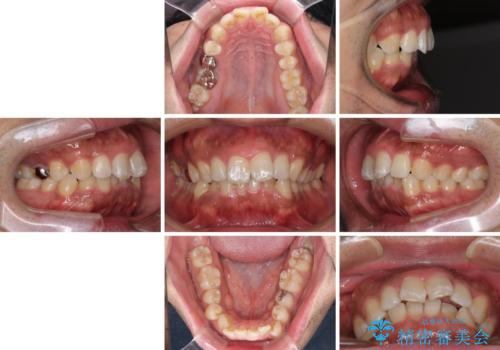

- 上下前歯部の叢生を気にして来院された患者様です。

レントゲン撮影により、右上奥歯が折れていることが分かりました。

患者様自身も何となく違和感を覚えていたとのことで、インプラント補綴治療を行うこととしました。

歯列不正は比較的軽微であったので、インビザラインによる矯正治療とし、矯正治療中にタイミングを見て抜歯とインプラント埋入を行う予定としました。